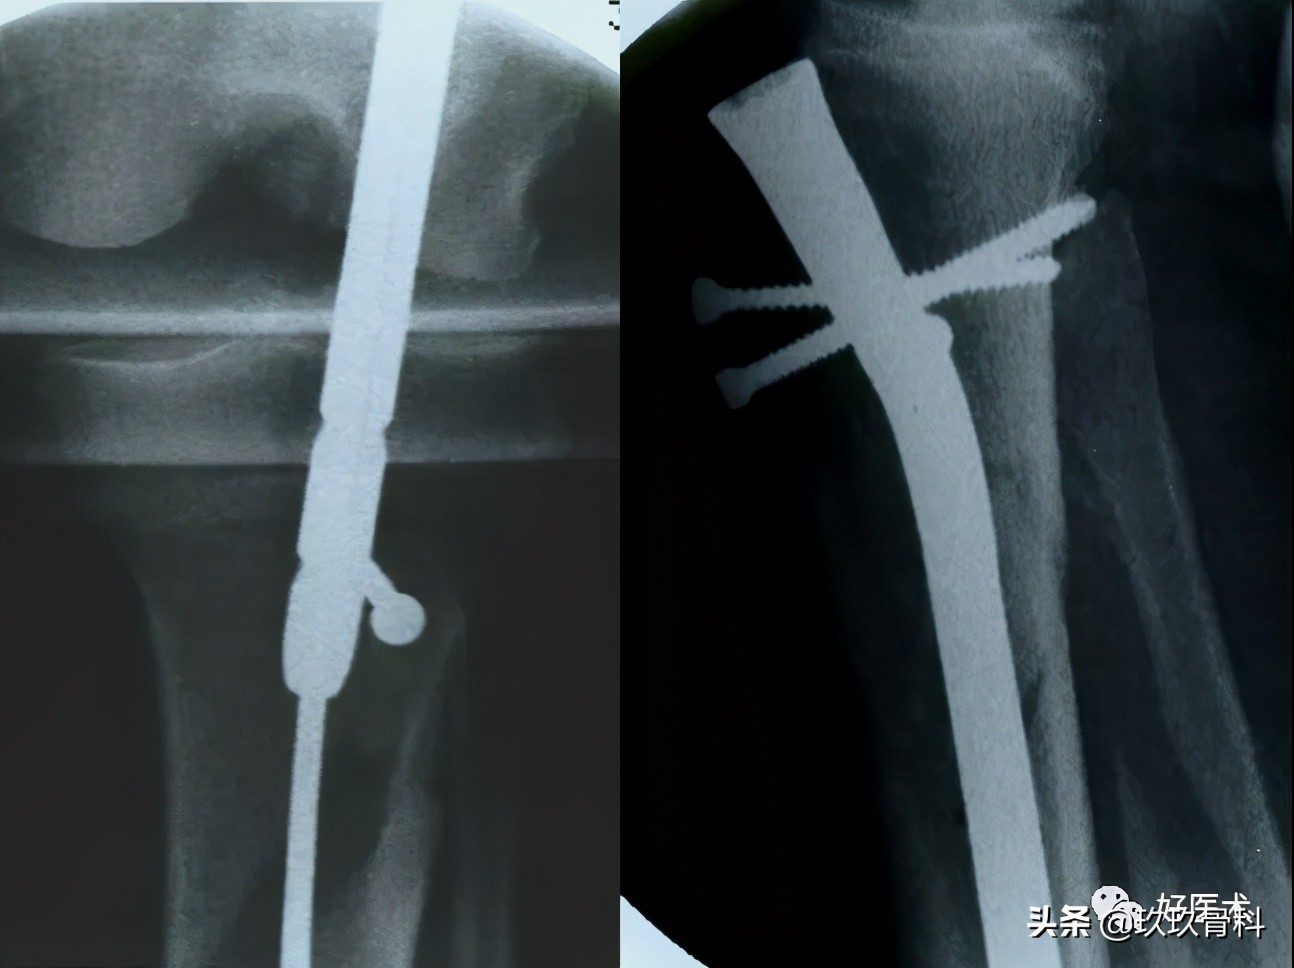

(八)固定技术/交锁

交锁钉:

- 扩髓髓内钉→建议锁钉

- 非扩髓髓内钉→强制锁钉

稳定骨折:

- 动力方式锁定→轴向加压;防止旋转

远端锁钉:徒手或瞄准器技术

近端锁钉:瞄准器

锁钉数目:

远端≥ 2(股骨)或3(胫骨)枚

原因:

- 髓内钉和锁定间非紧密接触→活动→冠状面不稳或力线异常

- 插入2或3枚螺钉,螺钉之间的不平行可减少这种活动。